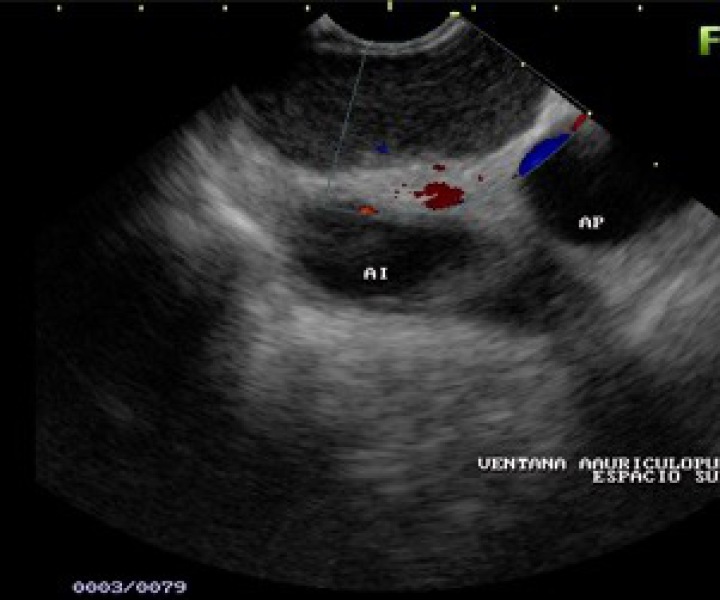

Ecoendoscopia o Ultrasonografía. USE

Es una técnica que combina la endoscopia con la ecografía para conseguir cortes ecográficos desde el interior del tubo digestivo en todos los planos del espacio y en todas las localizaciones donde llega el endoscopio.